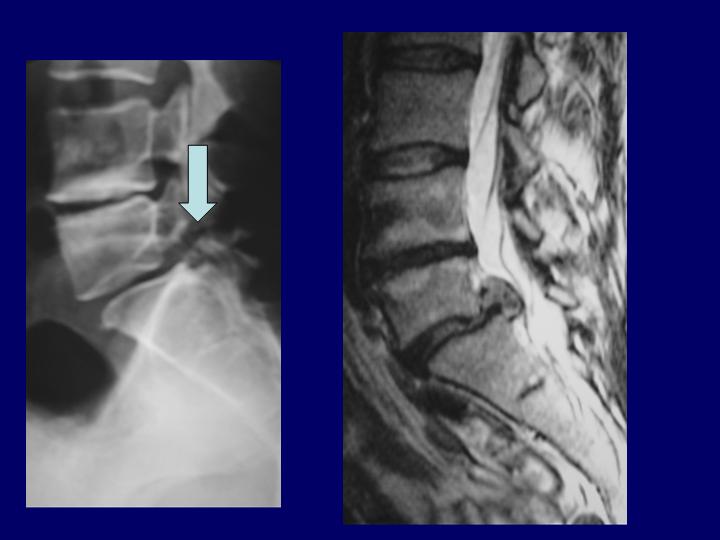

Hernias Discales